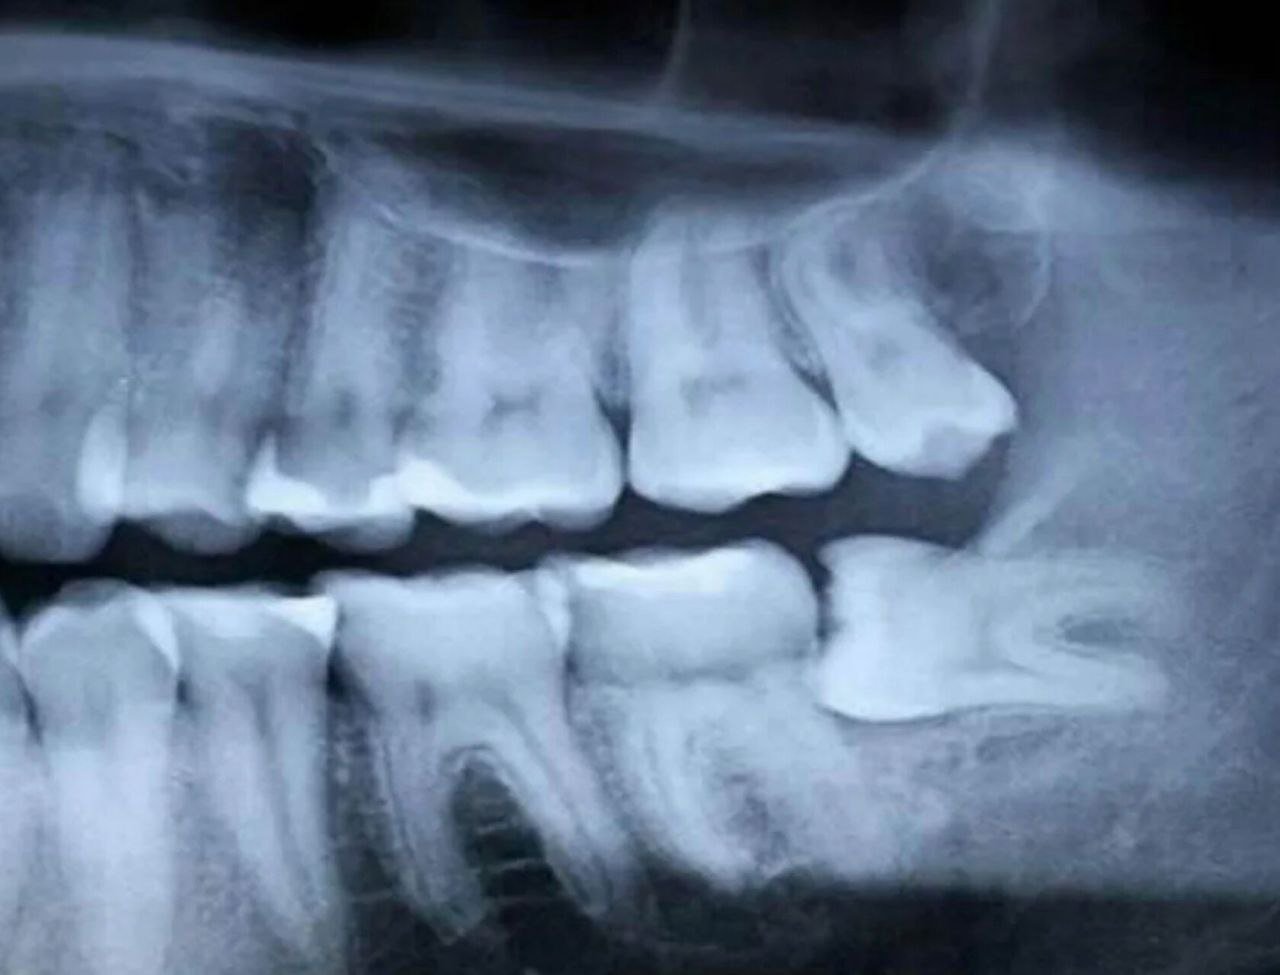

Пару недель назад, спустя 25 лет после этого случая, я получил неожиданное продолжение своей истории о «мудрости». Странная боль в нижней челюсти выявила еще один зуб мудрости, застрявший в десне, причем не вертикально, а горизонтально. Когда я показал рентгеновский снимок своей знакомой, она пошутила, что это «латеральная мудрость». Воистину, мы часто обладаем знаниями, но нам не хватает мудрости, чтобы применить их в своей жизни, и такое неправильное применение приводит лишь к путанице, хаосу и боли.

В этот раз я поступил не в «духовном» смысле, а просто и практично — назначил операцию и удалил этот пережиток далекого прошлого человечества в кресле стоматолога. Сейчас я восстанавливаюсь, сплевываю кровь и чувствую себя относительно довольным. В ближайших планах — удаление последнего (четвертого) зуба мудрости, который, как подтвердил мой стоматолог, нуждается в удалении, так что я наконец-то смогу назвать себя сертифицированным «не-мудрым» человеком.